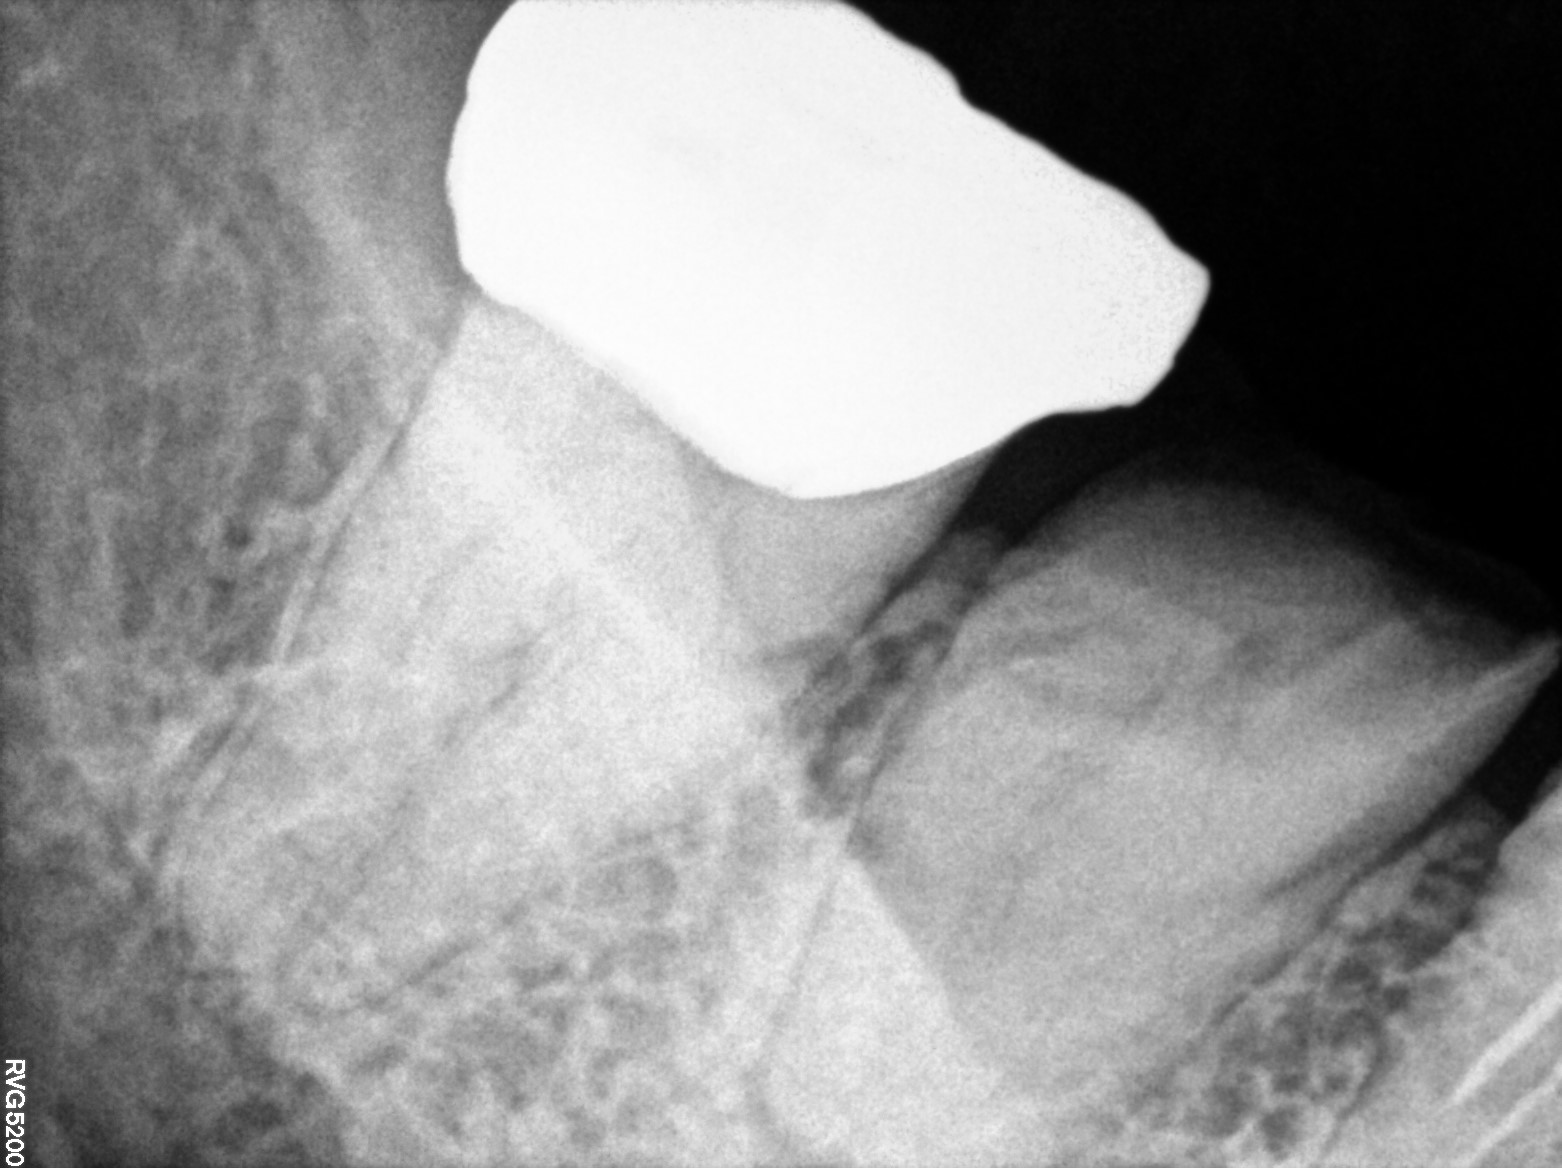

Dental Radiographs FHIR: DocumentReference · LOINC 24641-7

d (14).jpg

24641-7